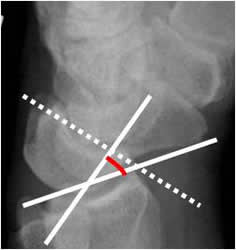

Angulo grandelunado:

Con una amplitud normal entre 0º y 30º. El eje del hueso grande se traza de la parte media de la cabeza, a la parte mas inferior de su superficie articular.

Fig 53. Angulo grandelunado.

A: Rx lateral de muñeca. Intersección entre los ejes de los huesos grande y lunado.